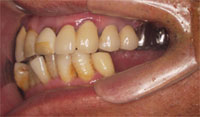

奥歯に入れている「入れ歯が合わない、噛めない」患者様の症例

口内写真

吉本歯科医院では、口内写真とパノラマレントゲンを撮影し、まずは顎の骨の状態まで詳しく確認しました。.

院長の吉本の診断は、次の3つでした。

・入れ歯では合わない、噛めないのは当たり前

・合わない入れ歯を入れているために骨がどんどん退縮していっている

・入れ歯を入れたり入れなかったりするため、歯並びがどんどん崩れだしている